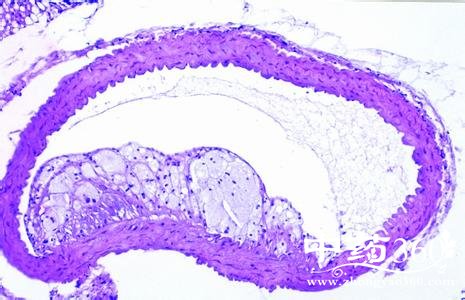

别谈胆固醇色变----许多人谈起胆固醇都色变,甚至不敢吃动物性食物。实际上,胆固醇是人体细胞膜不可缺少的成分,具有重要的生理功能,并非越少越好。健康成人一天摄入一个鸡蛋所含胆固醇的分量也不为多,儿童尤其需要补充胆固醇 。